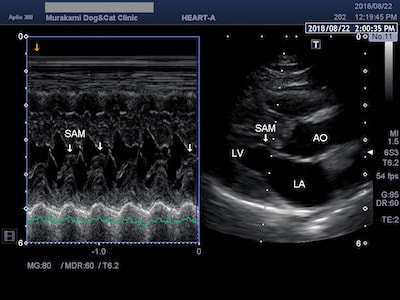

僧帽弁前尖収縮期前方運動(SAM)

HCMのなかには、僧帽弁前尖収縮期前方運動(SAM)と呼ばれる僧帽弁の異常な運動により、左心室から流出する血液の通路を妨害したり(左室流出路閉塞)、異常な弁の動きにより僧帽弁逆流を伴うものがあります。このようなHCMは閉塞性肥大型心筋症(HOCM)と呼ばれています。

SAMによる僧帽弁逆流

閉塞性肥大型心筋症(HOCM)は、SAMによる左室流出路閉塞と僧帽弁逆流を伴うため、左心房圧が上昇し肺水腫や血栓症のリスクが高まります。治療には血管を拡げて心臓の負担をとるための血管拡張薬や、尿を出して鬱血を改善するための利尿剤、血栓予防のお薬などを使います。

SAMによる左室流出路閉塞

異常な動きをする僧帽弁により左室流出路閉塞が起こると、左心室から流出する血流(大動脈血流)に高速血流が生じます(ホースの先端を摘むと水が勢いよく出るイメージ)。SAMの場合は左室流出血流波形がダガーシェイプ(ダガーナイフ型)になるのが特徴です。治療には左室流出路閉塞を緩和する目的で心拍数を抑えるお薬を使います。